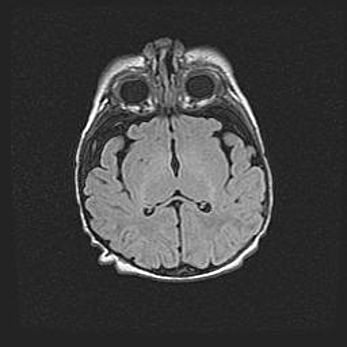

Лейкомаляция с кистозно-глиозной дегенерацией головного мозга.

Возраст: 2 месяца 25 дней

Вес: 6400 г

Окружность головы: 40 см

Срок гестации: 41 неделя

Лейкомаляцию относят к ишемически-гипоксическим повреждениям головного мозга, диагностируемым у новорожденных. При лейкомаляции в головном мозге обнаруживают очаги некроза, возникшие после тяжелой гипоксии и нарушения кровотока. В процессе морфогенеза очаги проходят три стадии: 1) развития некроза, 2) резорбции и 3) формирования глиозного рубца или кисты. Перивентрикулярная лейкомаляция (ПЛ) встречается примерно в 12% случаев среди новорожденных, обычно – у недоношенных детей, причем, частота ее зависит от массы, с которой младенец появился на свет. Наибольшее число малышей страдает лейкомаляцией, если масса при рождении 1500-2500 г.